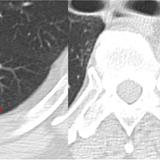

Gallery Lobar Collapse

Lobar Collapse

LUL Collapse

Album: LUL Collapse